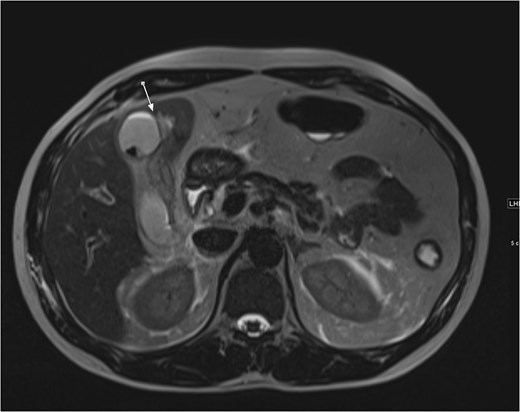

An ultrasound of the abdomen showed an impacted stone at the neck of the gallbladder with acute cholecystitis. The patient was admitted and started on IV antibiotics. He developed tachycardia reaching 110 bpm and had a high white blood cell count; therefore, the decision was made to proceed with a contrast-enhanced computed tomography (CT) scan, which showed evidence of acute cholecystitis and left PVT (Fig. 1). The medical team was consulted, and IV heparin without bolus was started. The gastroenterology team was consulted for his high bilirubin levels and advised for magnetic resonance cholangiopancreatography (MRCP), which was done the next day and confirmed the findings of left PVT (Fig. 2). MRCP also showed a micro perforation of the gallbladder and no biliary obstruction or stones (Fig. 3).

Axial cut MRCP showing T2-weighted images. Arrow indicates area of micro-perforation and small collection.